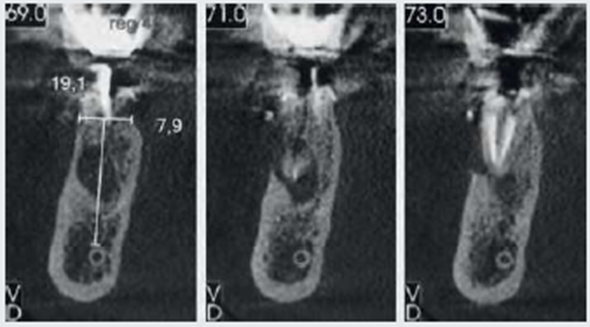

Um paciente do gênero masculino com 62 anos de idade, sem comorbidades, buscou tratamento odontológico relatando incômodo na região do dente 46, que possuía uma coroa provisória. Ao exame clínico, havia leve retração gengival ao redor do elemento dentário (Figura 1). Após os exames de TCFC e radiografia panorâmica, foram detectadas fratura radicular e lesão periapical correspondente (Figura 2).

Após oito meses, o paciente realizou uma nova TCFC, sendo visualizado um ganho em volume na região do elemento 46 em comparação ao exame inicial (Figura 9). Seguiu-se então um segundo tempo cirúrgico. Após todos os passos de antissepsia e anestesia, foram realizados incisão em rebordo alveolar e descolamento para visualização do tecido neoformado. Em seguida, foi realizada a fresagem seguindo a sequência recomendada pelo fabricante para a inserção do implante dentário (4mm x 11mm, Maestro Hl Switch, Implacil De Bortoli), sendo iniciada com a fresa lança helicoidal subsequente das fresas cônicas com dimensões de 3,5mm x 11mm e 4mm x 11mm.